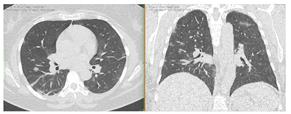

2. Наличие клинических проявлений, указанных в п. 1, в сочетании с характерными изменениями в легких по данным компьютерной томографии (КТ) (см. Приложение 1 настоящих рекомендаций) вне зависимости от результатов однократного лабораторного исследования на наличие РНК SARS-CoV-2 и эпидемиологического анамнеза.

- Изменения при КТ (рентгенографии), типичные для вирусного поражения (объем поражения минимальный или средний; КТ 1-2)

- Изменения в легких при КТ (рентгенографии), типичные для вирусного поражения (объем поражения значительный или субтотальный; КТ 3-4)

- Изменения в легких при КТ (рентгенографии), типичные для вирусного поражения критической степени (объем поражения значительный или субтотальный; КТ 4) или картина ОРДС.

КТ имеет высокую чувствительность в выявлении изменений в легких, характерных для COVID-19. Применение КТ целесообразно для первичной оценки состояния ОГК у пациентов с тяжелыми прогрессирующими формами заболевания, а также для дифференциальной диагностики выявленных изменений и оценки динамики процесса. КТ позволяет выявить характерные изменения в легких у пациентов с COVID-19 еще до появления положительных лабораторных тестов на инфекцию с помощью МАНК. В то же время, КТ выявляет изменения легких у значительного числа пациентов с бессимптомной и легкой формами заболевания, которым не требуется госпитализация. Результаты КТ в этих случаях не влияют на тактику лечения и прогноз заболевания при наличии лабораторного подтверждения COVID-19. Поэтому массовое применение КТ для скрининга асимптомных и легких форм болезни не рекомендуется.